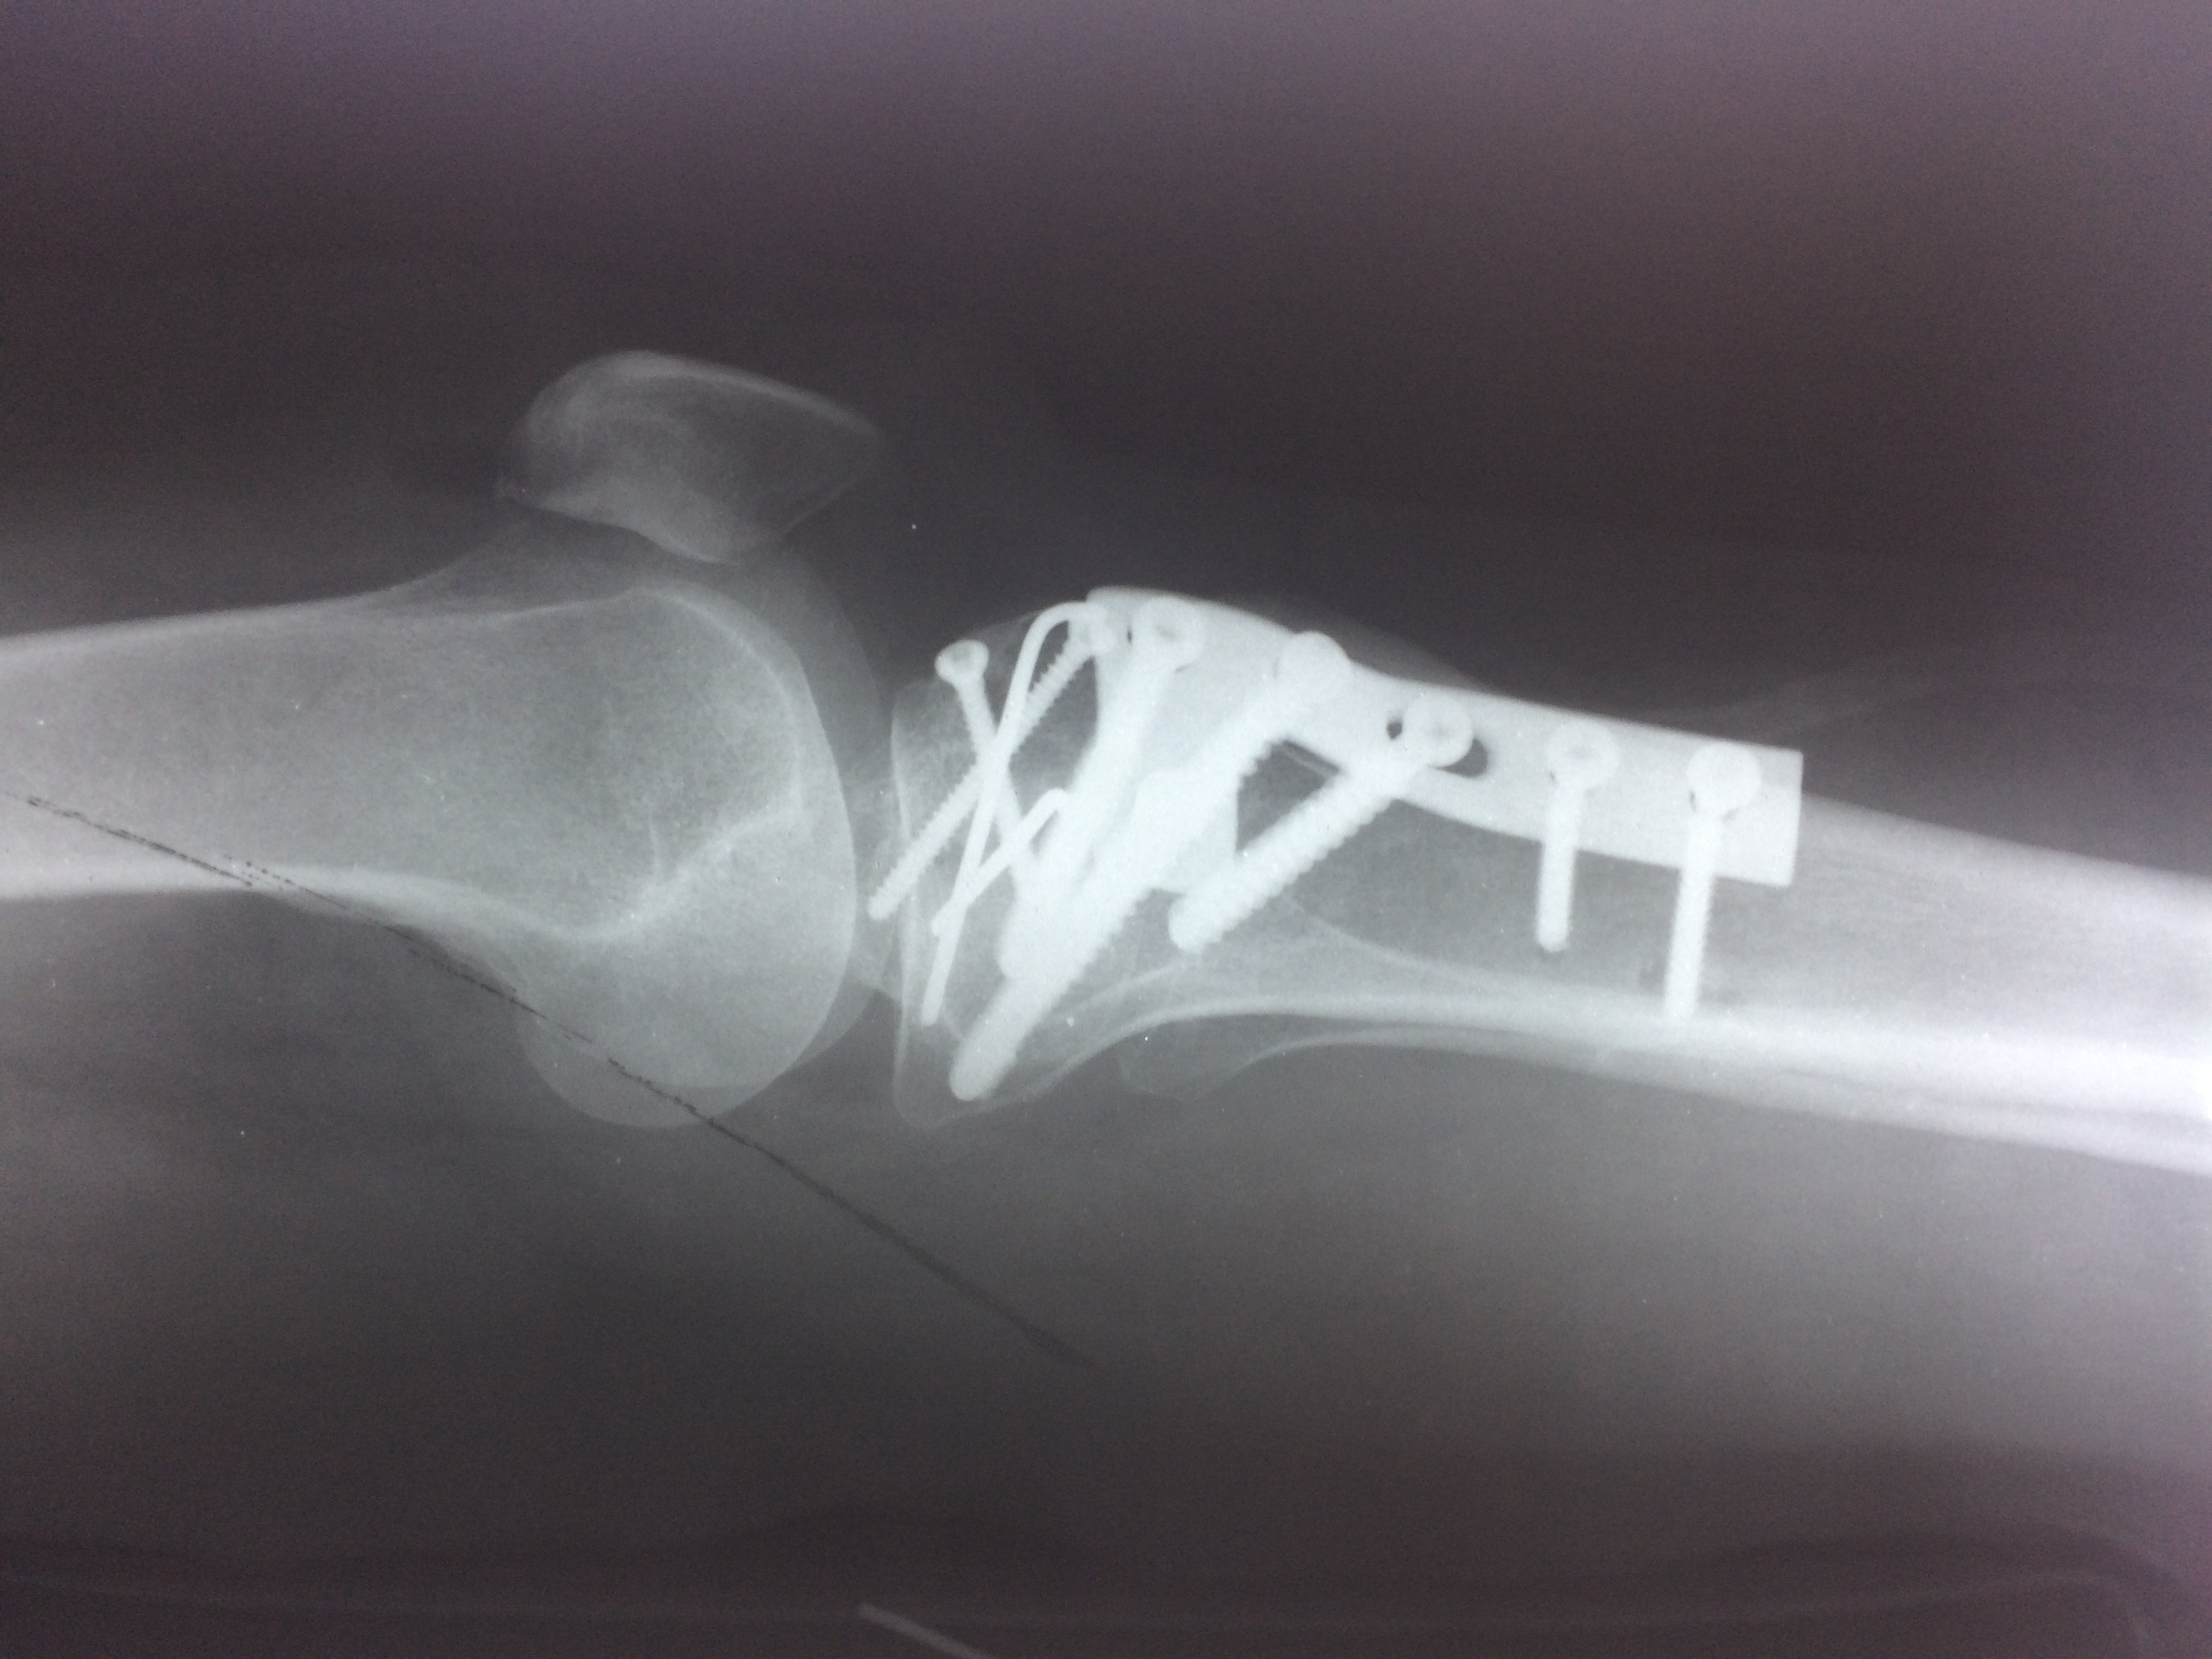

Перелом большой берцовой кости - серьезное повреждение, сопровождающееся болезненными ощущениями и нарушением функции ноги. На этой странице вы найдете много фотографий, позволяющих вам более детально изучить эту травму.

Медицинские изображения

Здесь представлены медицинские изображения переломов большой берцовой кости, сделанные врачами в процессе диагностики и лечения. Вы сможете увидеть, как выглядит этот тип травмы на рентгеновских снимках и других медицинских изображениях.